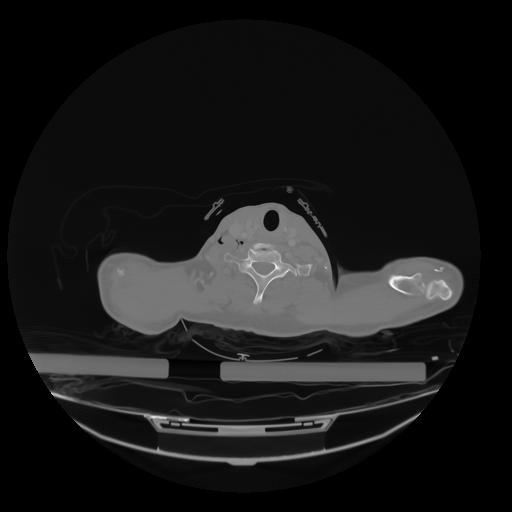

28 CUERPO,CE,Vol,2.0,CUERPO,,